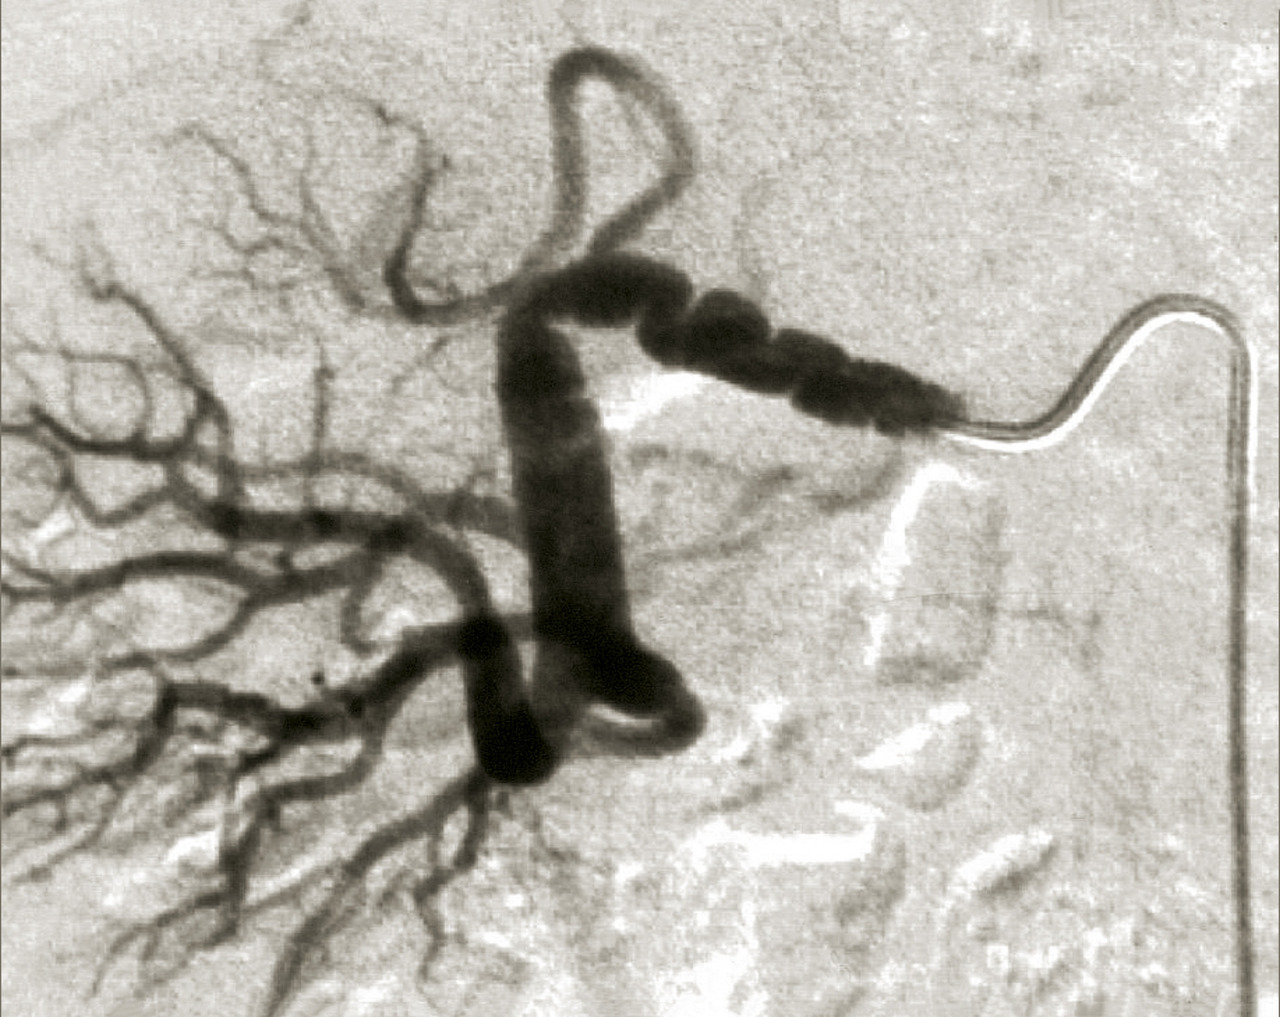

L’échographie-Doppler, l’angio-tomodensitométrie (angio-TDM [fig. 2] et l’angio-imagerie par résonance magnétique (angio-IRM) [fig. 3] permettent le diagnostic de sténose de l'artère rénale. Ils estiment à la fois le degré de sténose (exprimé en pourcentage de réduction du diamètre) et l’impact sur la vascularisation d’aval. Ces 3 examens sont validés et recommandés en première intention. Leur utilisation dépend de l’accessibilité et des habitudes locales. Il est à noter que l’écho-Doppler, très sensible et spécifique dans la sténose de l'artère rénale athéromateuse sous réserve d’un opérateur entraîné, est de sensibilité imparfaite dans la fibrodysplasie, dans laquelle l’angio-TDM est l’examen de référence.

Le tableau résume les avantages et inconvénients respectifs des 3 examens de référence. L’artériographie est réservée aux revascularisations (fig. 4), et n’a pas de place à titre diagnostique.

En cas de fibrodysplasie, les lésions sont multiples, distales, souvent bilatérales, avec aspect en « collier de perles » (fig. 4). Il est recommandé, dans cette pathologie qui est souvent multifocale, de rechercher d’autres lésions artérielles (sténoses ou anévrismes) au niveau des artères digestives, cervicales et intracrâniennes.